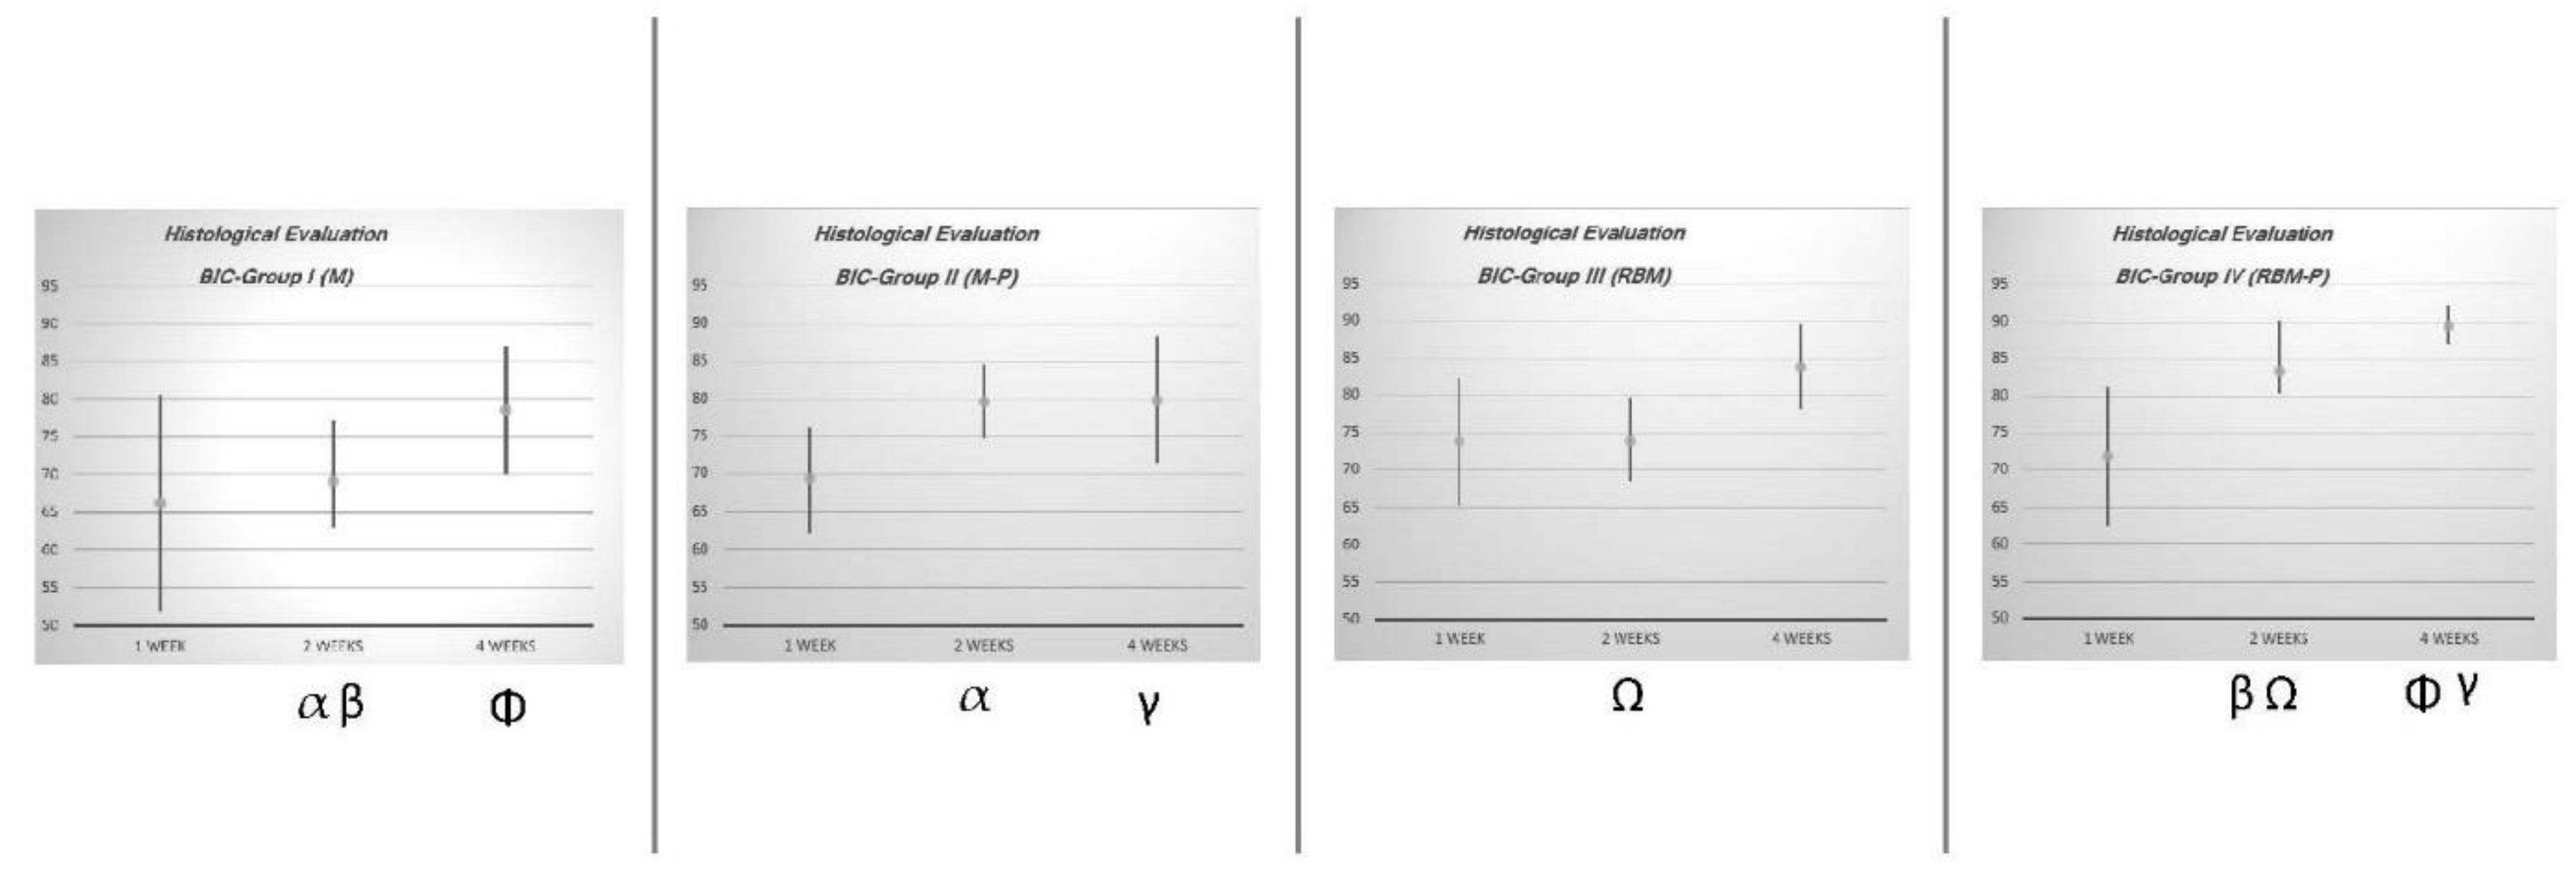

| Experimental Group | n | 1 Week | 2 Weeks | 4 Weeks | |||

|---|---|---|---|---|---|---|---|

| BIC (%) | C.I. 95% | BIC (%) | C.I. 95% | BIC (%) | C.I. 95% | ||

| I (M) | 12 | 66.20 | 51.89–80.51 | 69.06 α β | 62.93–77.19 | 78.56 Φ | 70.10–87.02 |

| II (M-P) | 12 | 69.27 | 62.20–76.34 | 79.66 α | 74.75–84.57 | 79.92 γ | 71.46–88.38 |

| III (RBM) | 12 | 73.90 | 65.27–82.53 | 73.97 Ω | 68.34–79.60 | 83.91 | 78.20–89.62 |

| IV (RBM-P) | 12 | 71.92 | 62.55–81.29 | 83.35 β Ω | 80.47–90.23 | 89.49 Φ γ | 86.82–92.16 |